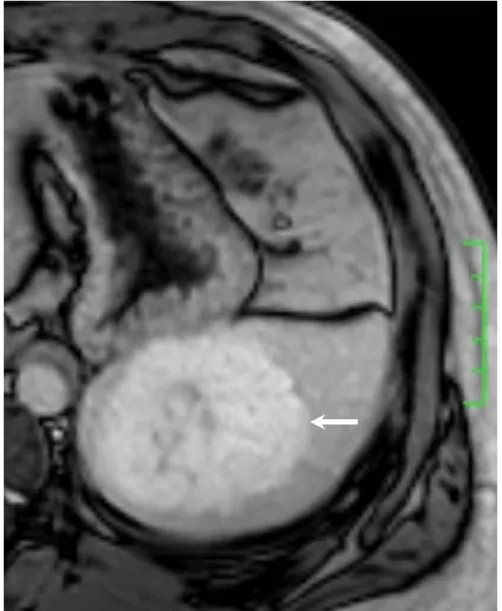

Solitary well-circumscribed masses were detected in all the five patients by ultrasound. One mass was of hypoecho, while the remaining masses were of hyperecho with posterior enhancement (Figure 1A). The maximum diameter ranged from 3.0 cm to 9.0 cm. At CT scanning, two masses appeared as hypodense (Figure 1B) and one was isodense (Figure 2A) to the normal spleenic parenchyma. In the two patients who received MR imaging, masses were isointensity at T1 weighted images (Figure 3A) and hypointensity with scattered sign void spots at T2 weighted images (Figure 3B). After intravenous injection of the contrast materials, all the five masses presented circle enhancement at arterial phase (Figure 3C and Figure 4A), while peripheral enhanced node was noted in one mass (Figure 2B). The circle enhancement persisted and radical line enhancement were observed at portal vein phase in 3 cases (Figure 1C) and progressive filling in was seen in two cases (Figure 2C). At delay phase of MR imaging, one lesion showed obvious enhancement with stellate low signal scar in the center comparing with surrounding splenic parenchyma (Figure 3D), while the other demonstrated central and circle enhancement to form a spoke-like appearance (Figure 4B). At delay enhanced CT scanning, two masses were isoattenuation to the surrounding splenic parenchyma (Figure 2D) and one lesion kept as hypoattenuation but with radial enhanced lines and enhanced circle to form a spoke-like appearance.

At pathological examination, all the masses were well demarcated on gross cut surface. A central stellate scar with peripheral interspersed dark brown nodules and the whitish intervening fibrous bands was noted to form spoke-like appearance (Figure 3E), which was well correlated with CT and MR imaging findings at enhancement. Microscopically, these angiomatoid nodules were surrounded by dense concentric collagen fibrous stroma and dispersed stromal cells with oval-to-spindle nuclei and scanty cytoplasm (Figure 3F). The abunden fibrous stroma may result in hypointensity at T2 weighted MR images. Hemosiderin was noted in the angiomatoid nodules (Figure 3G), which might contributed to signal void at T2 weighted MR images.

It usually affects middle-aged adults [6] and it is commonly found incidentally on radiographic imaging, or during operation for an unrelated condition. In present series, the patients are middle-aged adults without any related symptoms and the lesions were detected incidentally at routine ultrasound of health examinations. On ultrasound, manifestations of SANTs are vary widely from heterogeneous echo-texture with hyperechogenic, hypoechogenic, or isoechogenic appearing lesions, which are unspecific [7,8]. CT and MRI can show some characteristic features of SANTs, which include a solitary well demarcated mass with early peripheral enhancemant with radiating lines and progressive enhancement at the delay phase, and hypointens at T2 weighted MR images [2,3,5,9-13]. These features reflect the underlying pathological changes of scattered angiomatoid nodules separated and surrounded by sclerotic fibrotic stroma [10]. In present series, we also observed these characteristic features with well correlation to pathological findings. Circle and spoke-like enhancement can be contributed to fibrotic stroma surrounding and separating the angiomatoid nodules. The sclerotic fibrotic stroma may also result in isodense on CT, isointensity on T1 weighted images and hypointensity on T2 weighted images of MR imaging. The signal void spots at T2 weighted MR images have not been described at other literatures and may be contributed to hemosiderin deposition due to magnetic susceptibilty artifact.